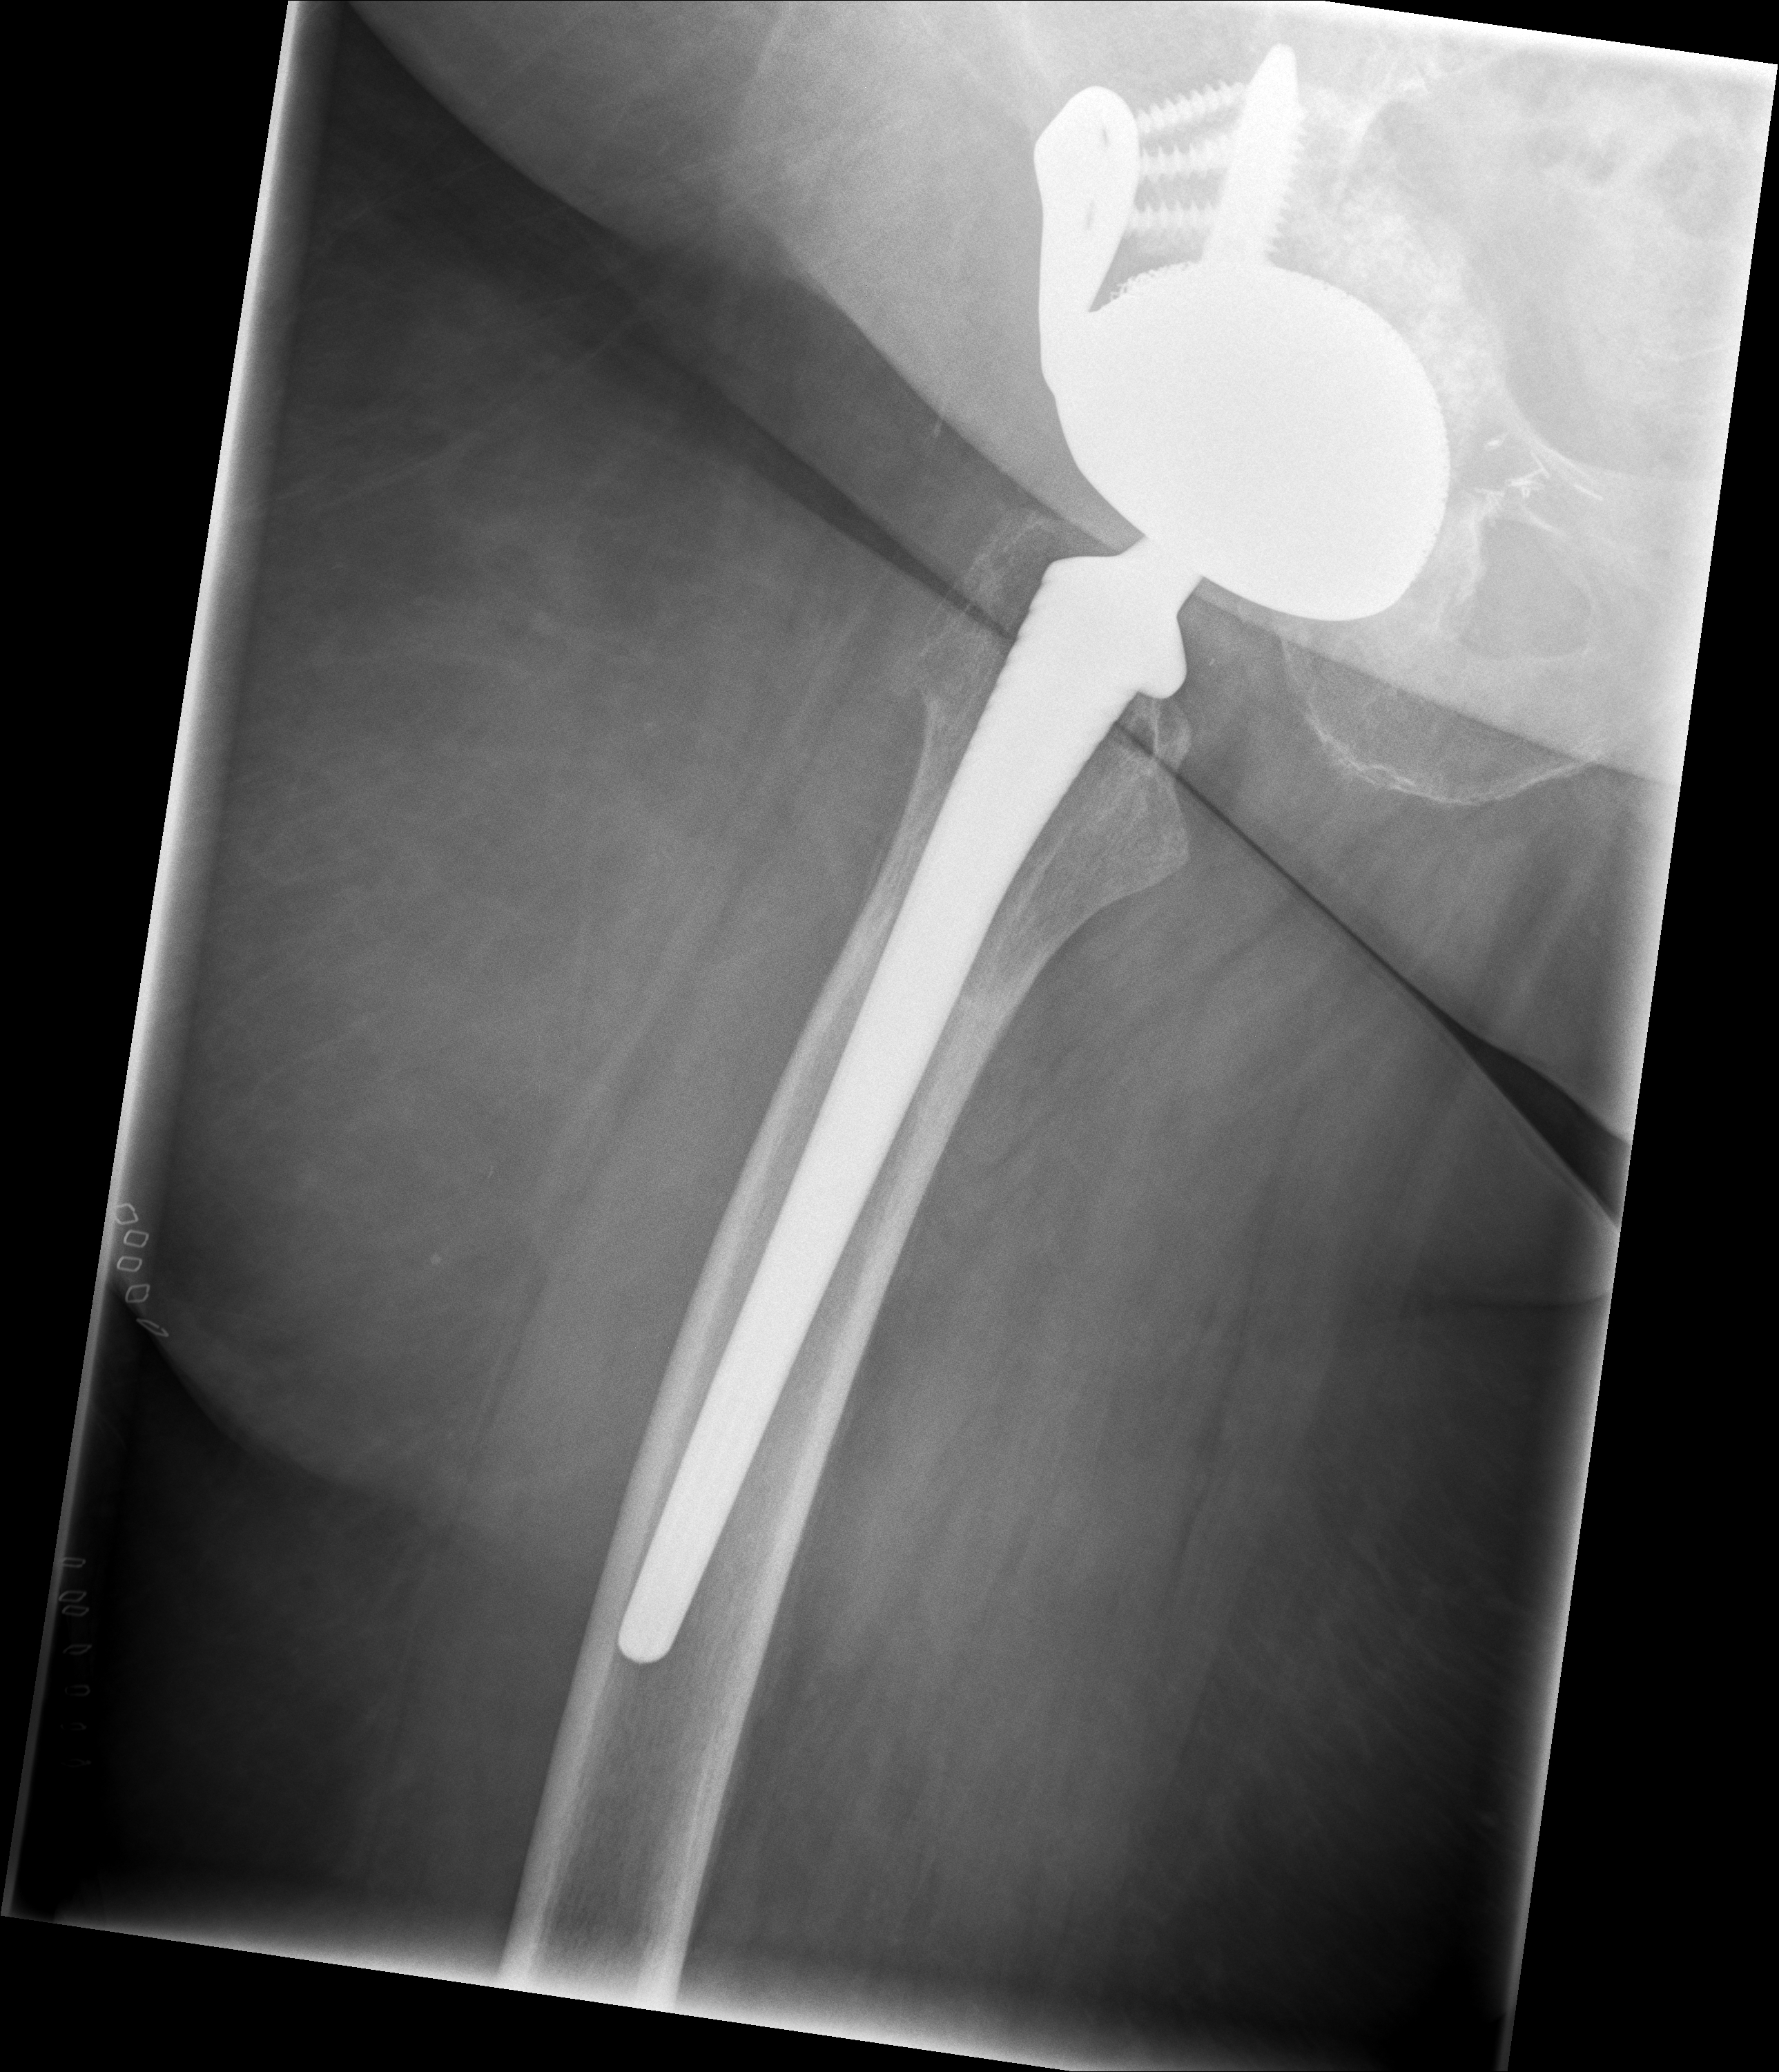

24.02.2026 - Postoperativ

Röntgen Becken + Hüfte rechts (Kontrolle nach Wiedereinbau)

3 Aufnahmen | Becken tief + 2x Hüfte Lauenstein | 5 Tage nach OP

Postoperative Röntgenkontrolle

Röntgen Becken tief + 2x Hüfte Lauenstein R – Kontrolle 5 Tage nach Wiedereinbau.

24.02.2026 - POSTOP

Röntgen Becken tief (nach Wiedereinbau)

DICOM

Kontrolle Becken 5 Tage nach Wiedereinbau TEP

Röntgen Hüfte Lauenstein R (1)

Kontrolle Hüfte 5 Tage nach Wiedereinbau TEP

Röntgen Hüfte Lauenstein R (2)